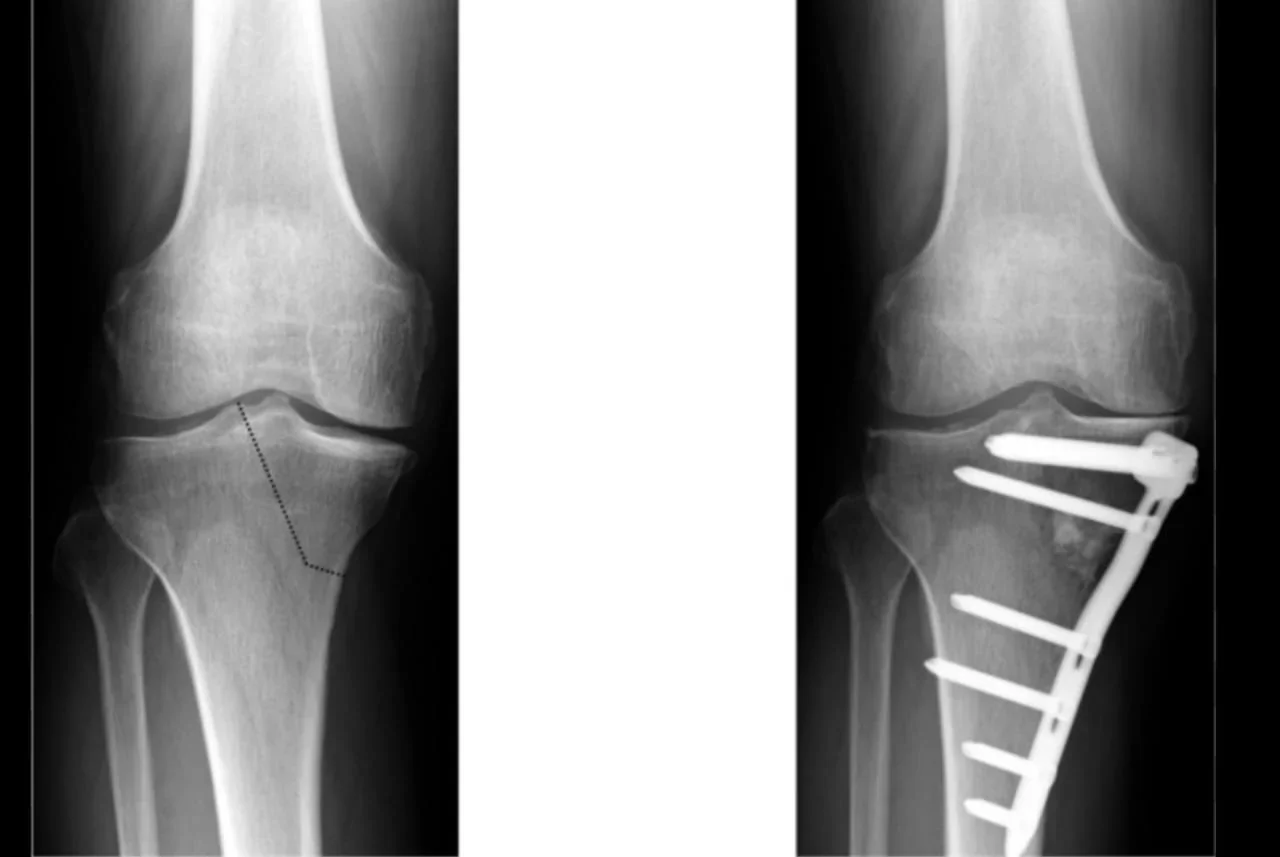

Precise Bone Correction

A controlled cut (osteotomy) is made at the top of the tibia. The collapsed part is lifted to restore the knee joint's natural shape and angle.

Fixation

A small metal plate and screws hold the bone in its new position.

- X-rays show collapse or depression of the inner side of the tibial bone.